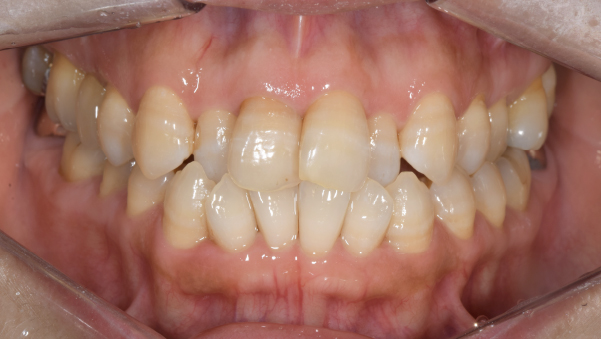

症例写真(治療前)

【担当医師所見】

治療前:

八重歯が目立ちます。また銀歯もおおく、見た目が気になります。虫歯も散見できます。